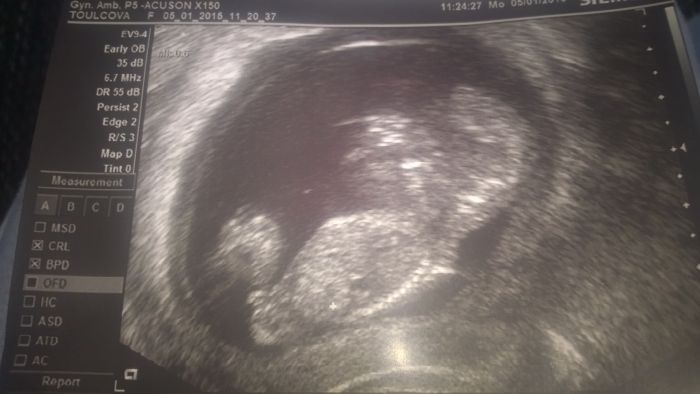

Tak my dneska screening v pořádku, máme kartičku, podle utz odpovídá 12+2 a jsme 11+6. Termín mám 21.7. a podle utz 18.7., ale do karty mi to sestra nenapsala. A zatím máme 2mm dlouhého pindíka, ale ještě to není stoprocentní. Ale obávám se, že mu už asi neupadne, podle toho, jak je velký a přečnívá. Manželovi vyhrkly slzy